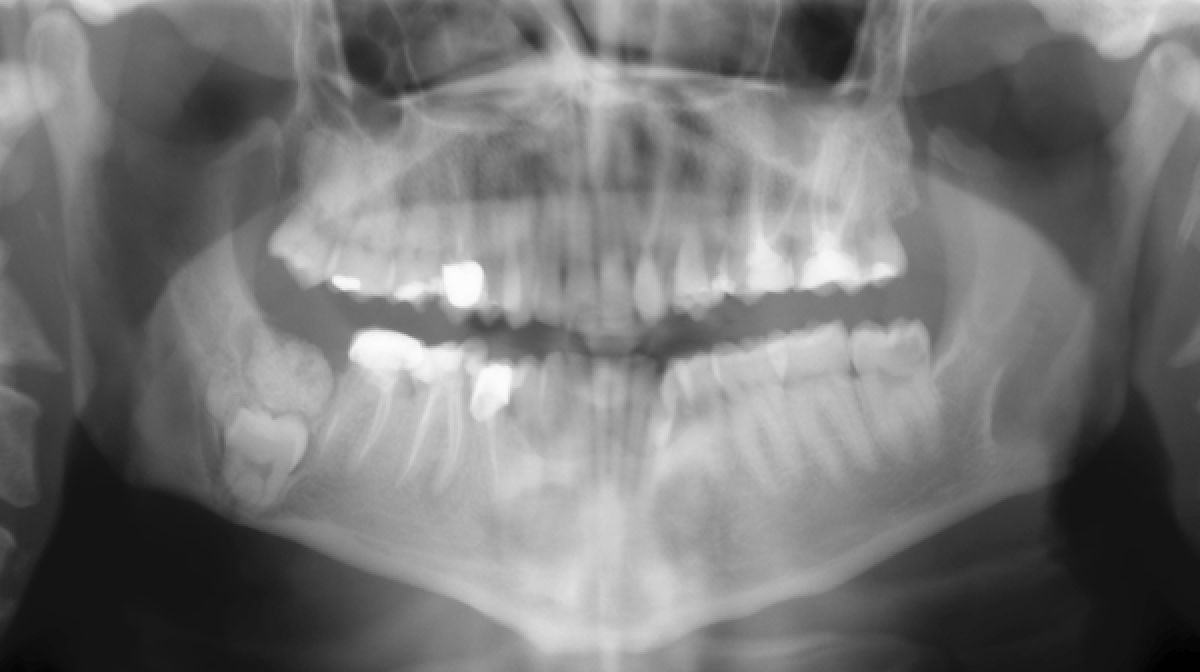

Benign osteoblastoma of the mandible in a 12‑year‑old female A case report